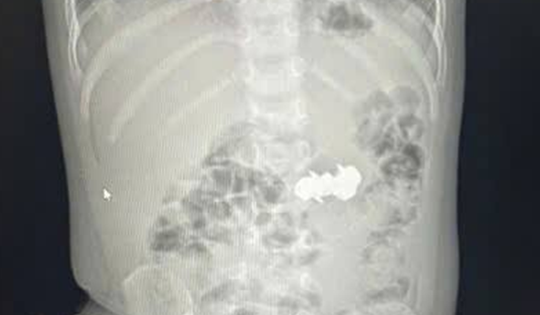

Bé trai 2 tuổi được gia đình đưa đi viện, bác sĩ gắp ra thứ "đáng sợ" bên trong